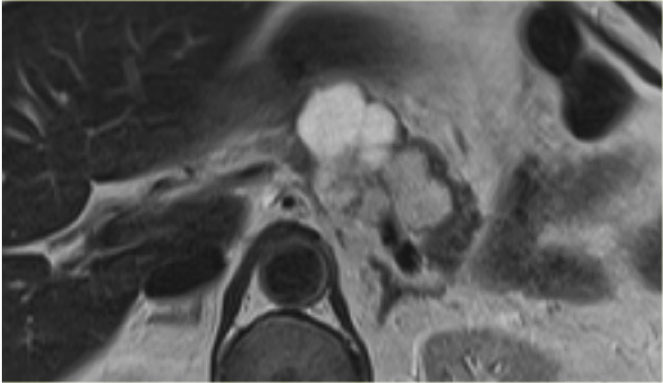

The image shows a T2WI of a 71 year old man with a history of weight loss and nondescript upper abdominal complaints.

This was initially thought to be a branch-duct IPMN, but turned out to be a SCN.

Notice the central hypointensity.

This is scar tissue in a SCN.

Notice also the characteristic lobulated surface.